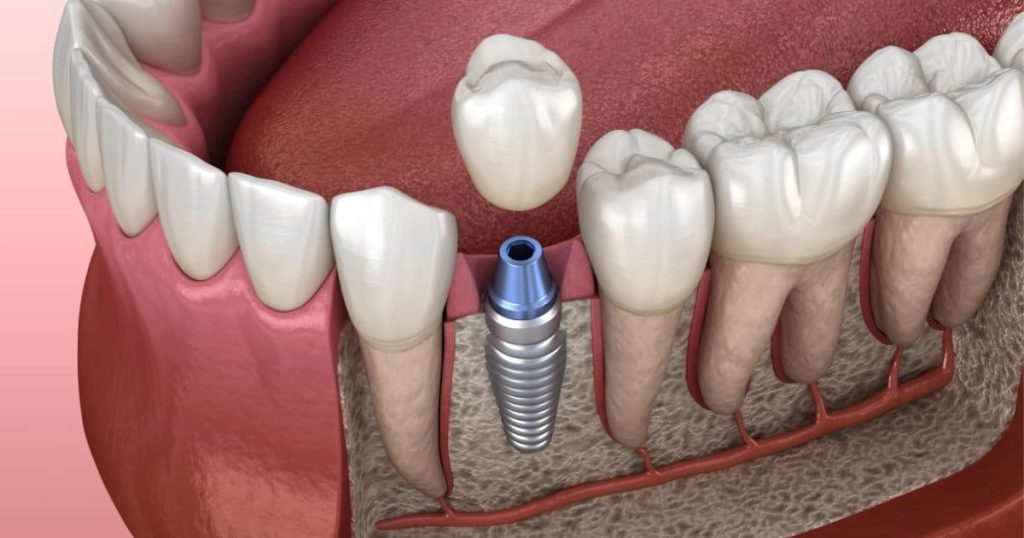

Dr. Jairo Chavez Diaz

- Implantes y Endodoncia